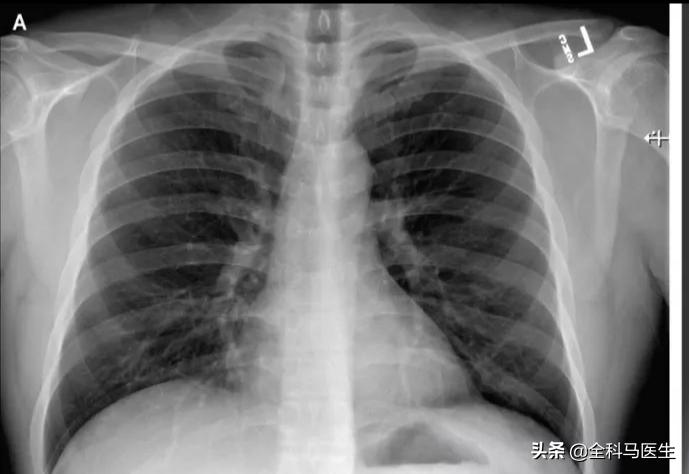

新冠病毒感染最常累及呼吸系统,重症者约在一周左右会出现缺氧的表现,如感觉呼吸困难、喘憋、胸闷,在吸氧下可能会缓解。当病情进一步进展至危重程度,肺部出现大面积受累,甚至呈现“白肺”,肺功能进一步下降,呼吸会越来越费力,吸氧也无济于事,需要借助于呼吸机帮助呼吸。

肺部影像学改变一般成像肺部毛玻璃样变和斑块样改变,如下图毛玻璃样改变